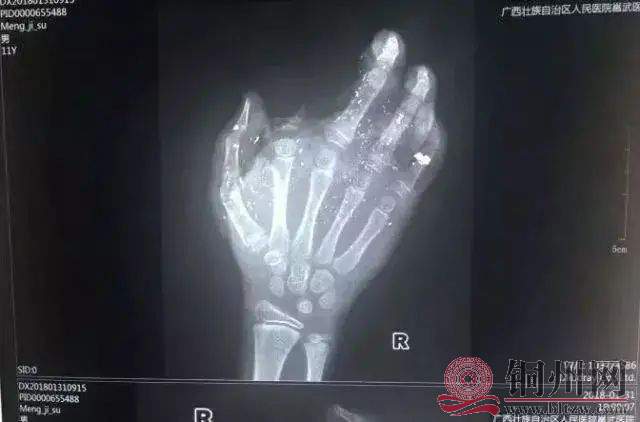

2018年1月31日,广西一小男孩手掌被充电的手机炸得血肉模糊,右手食指被炸没了,拇指、中指、无名指也都炸伤。

0006b5fe4970c4a4cf45252d65443c68.jpg